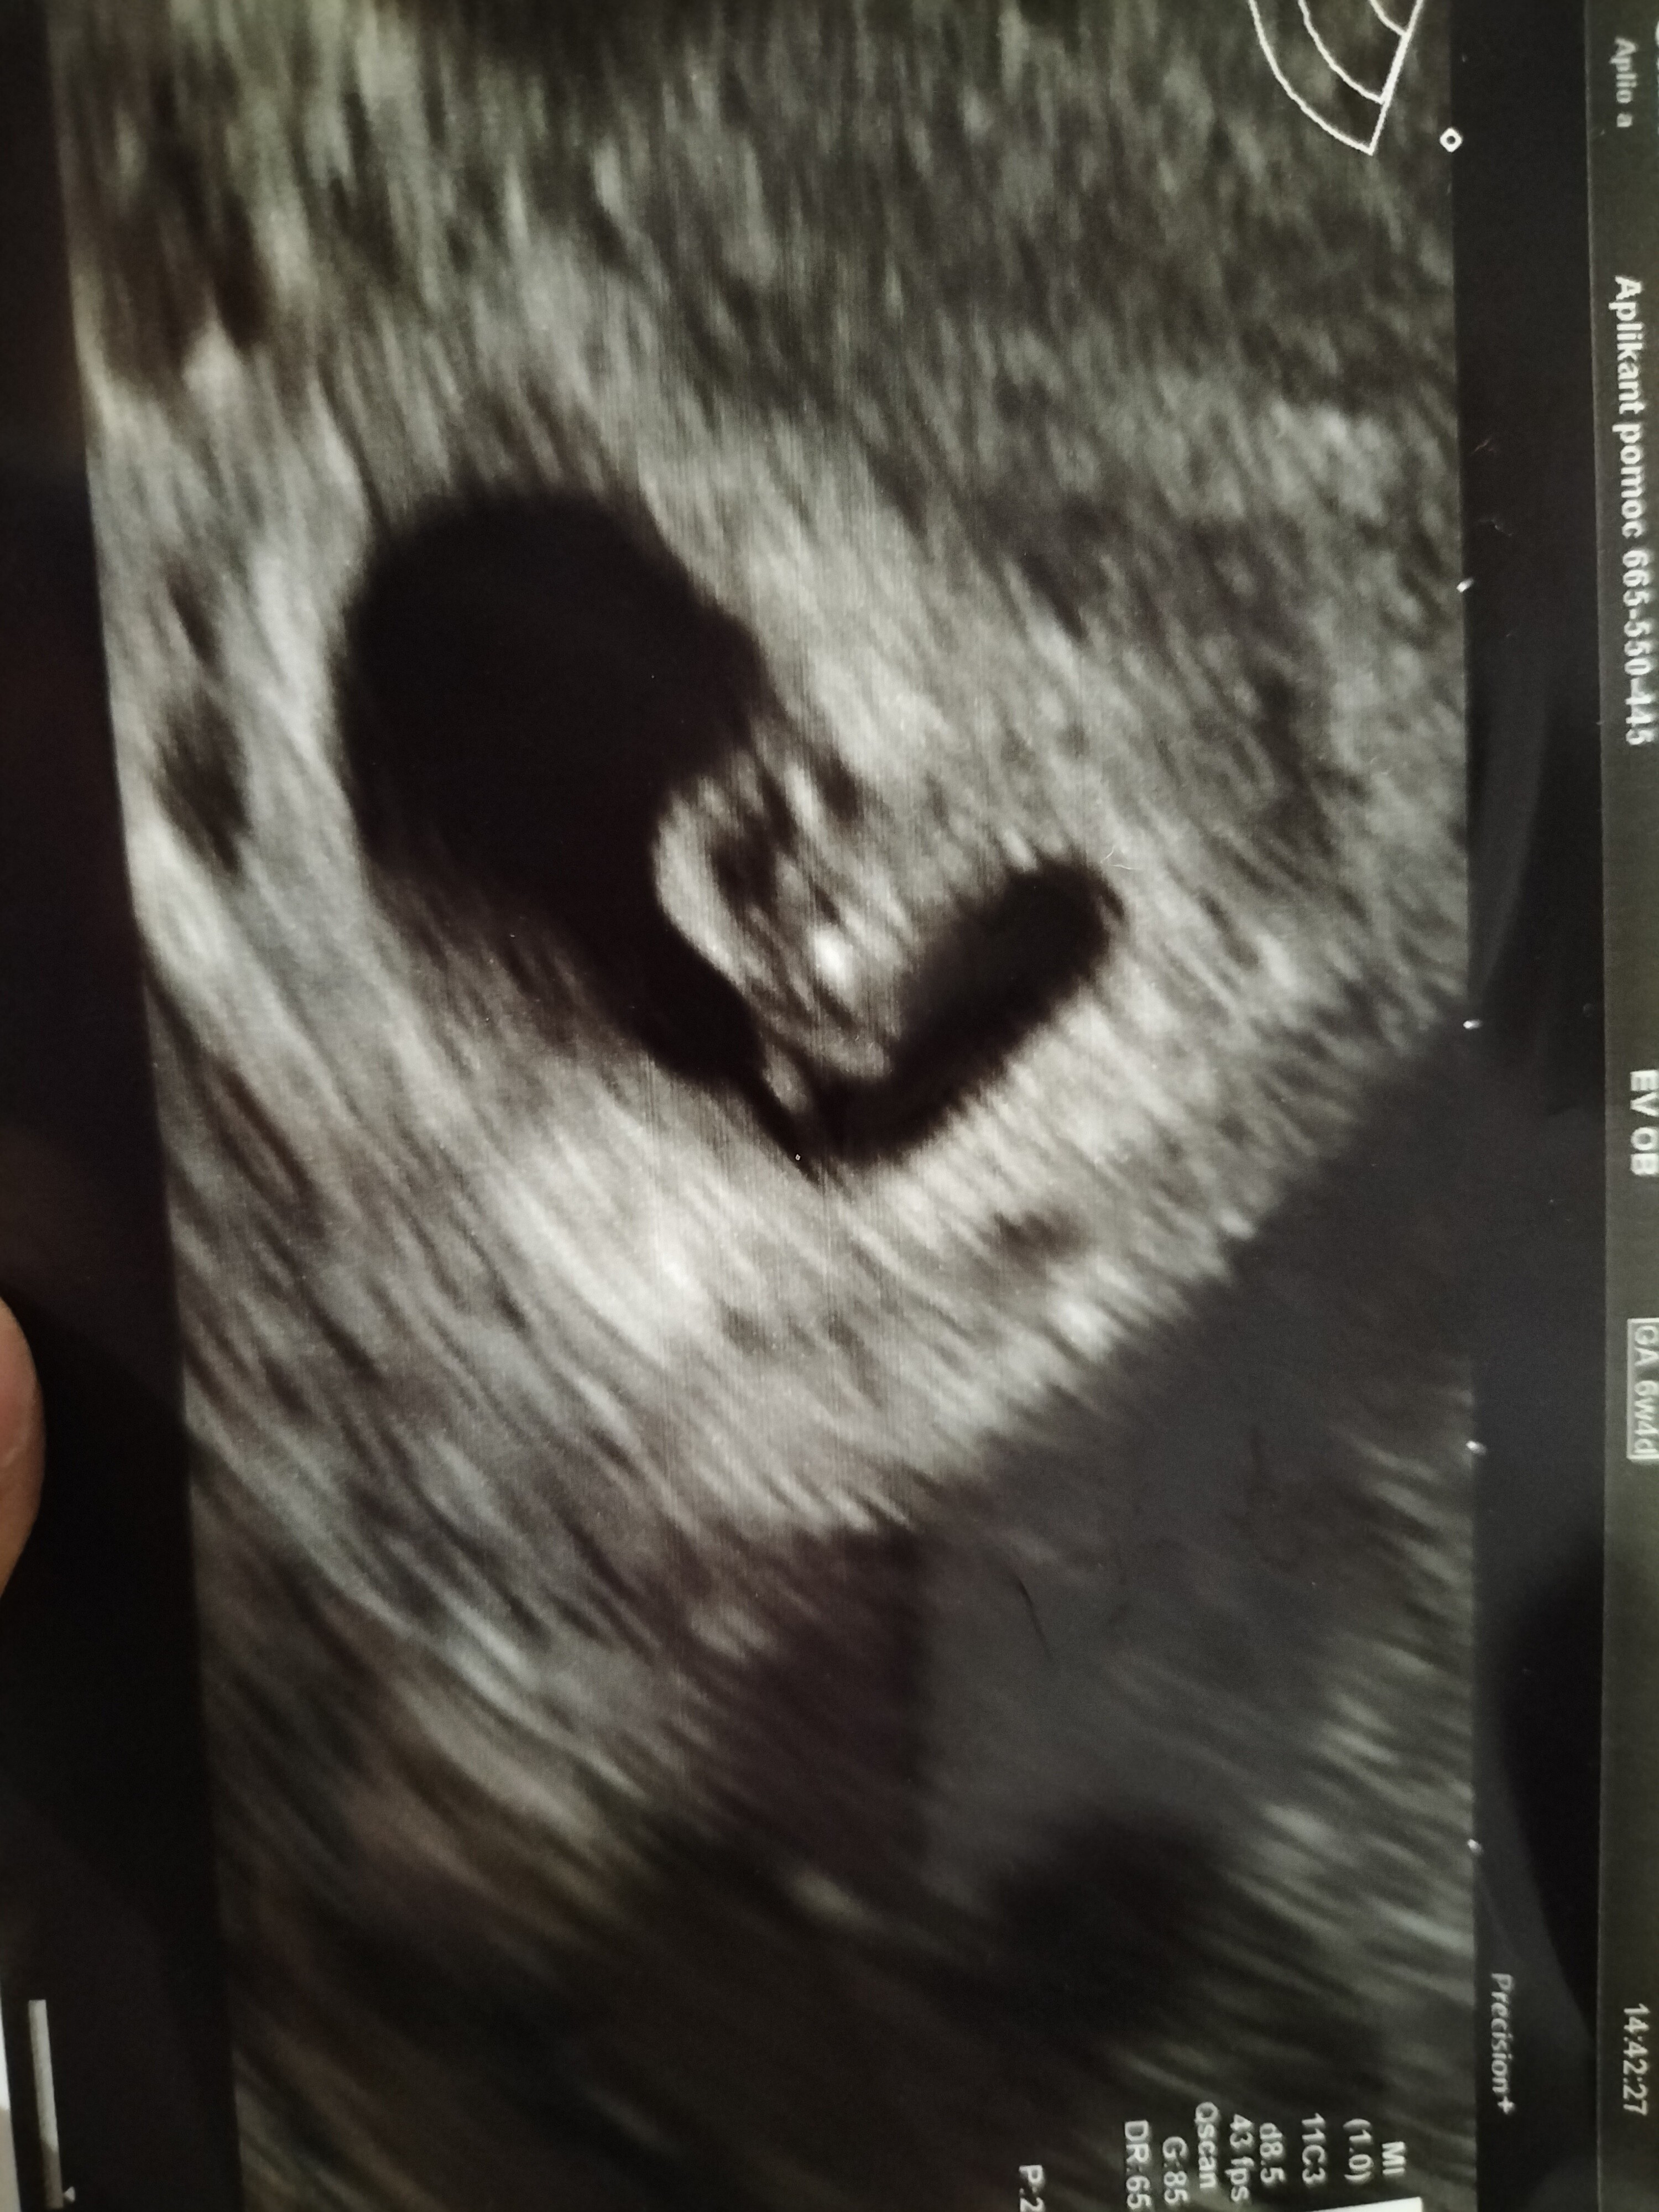

Cześć, ja już po wizycie. Widziałam serduszko, 118 uderzeń na minutę 😍. Dzisiaj 6+4. Mój mąż oczywiście nie wytrzymał i wszystkim się już chwali że dziecko mu się rodzi😂

Załączniki

• IMG20211115162620.jpg

IMG20211115162620.jpg

1,9 MB · Wyświetleń: 92